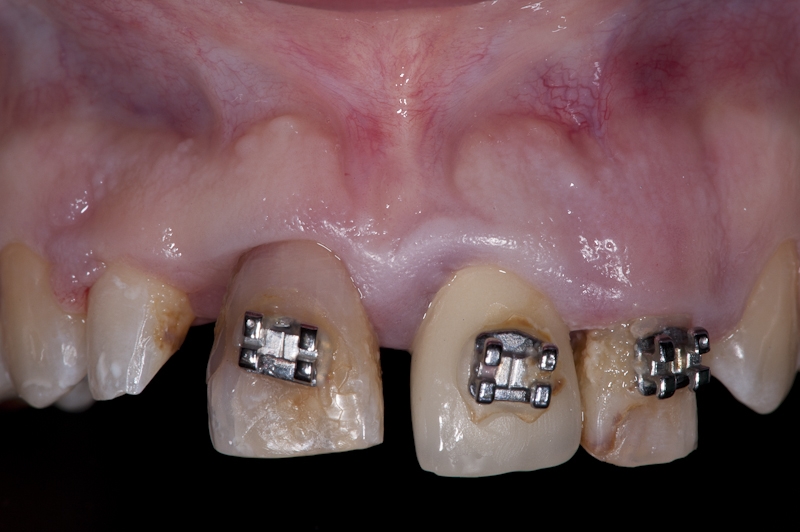

Left maxillary incisior with failing endodontic treatment despite apicoectomy which was done 15 years prior